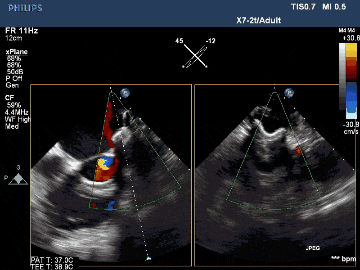

術后TEE影像示封堵完全

術后TEE三維重建影像示封堵器位置佳,封堵完全